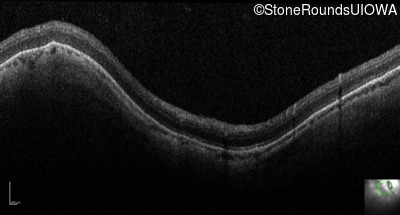

Optical Coherence Tomography - Right - 20/100

Exemplar